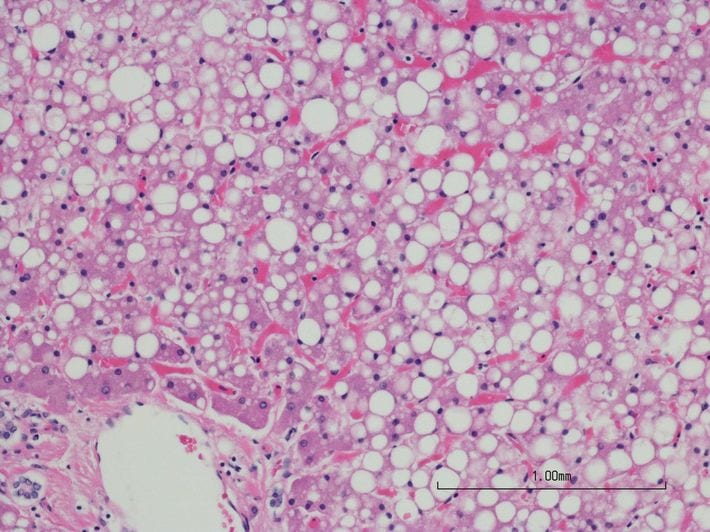

自覚症状はなく、血液診断では判定不能…人間ドックでなければ見つからない「脂肪肝」の恐ろしいリスク

※写真はイメージです